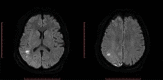

Patient and methods: We report the case of a 64-year-old woman with pneumococcal meningitis who developed parainfectious vasculitis causing ischaemic brain damage. Cerebral magnetic resonance imaging (MRI) confirmed the diagnosis. Clinical and radiological recovery after delayed addition of corticosteroid was achieved.

Discussion: This report shows that the onset of neurological deficits following pneumococcal meningitis can be caused by cerebral vasculitis. Underdosing with antibiotics and delayed adjunctive dexamethasone seem to favour this complication. There are no guidelines for treatment but high doses of steroids led to resolution in this case.